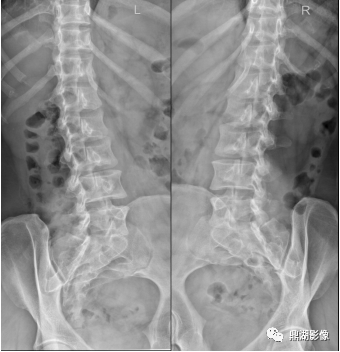

• 骨盆X线解剖详解

骨盆X线解剖详解